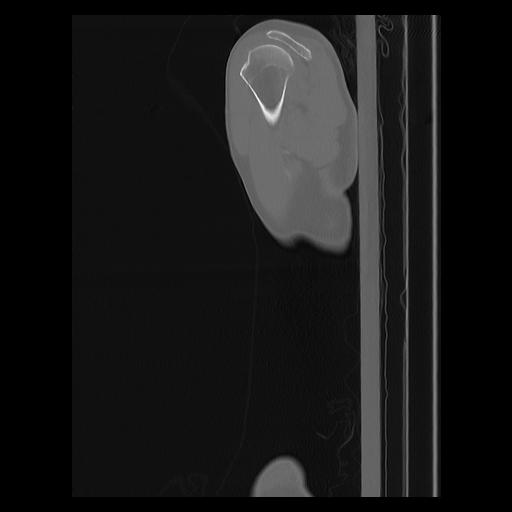

33 PULMON,CE,Sagittal,3.000,PULMON,Sagittal,